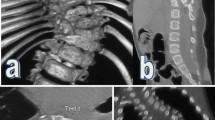

During the operation, heavy halo-femoral traction was maintained (Fig. 1), and somatosensory evoked potential (SEP) and motor evoked potential (MEP) were thoroughly utilized to monitor the spinal cord functions. After exposure of posterior spinal components through a midline incision, pedicle screws (or hooks) were placed in the key vertebrae’s and adjacent to them for providing multiple anchor points. Facet joint capsules, intertransverse ligaments and contracture soft tissues at the rigid segments were released completely. Then, distraction, compression, rod rotation, and derotation should be adopted for correction. All structural curves need to be fixed and fused. Allogenous or autogenous bone grafts could be implanted for fusion [8,9,10].

A patient with RCS accompanied by SCM. a-b Preoperative radiographs show that coronal Cobb angle was 62°.c-d Preoperative bending radiograph of the convex side shows that Cobb angle was 45.6° and flexibility was 26.45%.e Preoperative CT indicates mixed defects including failure of segmentation and formation. f-g Preoperative MRI indicates SCM type 2. h After heavy halo-femoral traction, the coronal Cobb angle was reduced to 38.2°.i-j After posterior-only surgical correction, postoperative radiographs show that coronal Cobb angle was 21.4°, and correction rate was 65.48%. k-l postoperative radiographs at 36 months after surgery show that coronal Cobb angle was 22.4°, and no signs of neurological impairment were found at the final follow-up stage